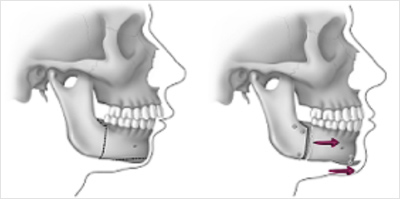

Correcting a retrusive jaw (too far back) and or a weak chin consists in performing a surgery on the lower jaw at the back and repositioning it with screws or wires. Surgery may be performed to change the appearance of the chin.